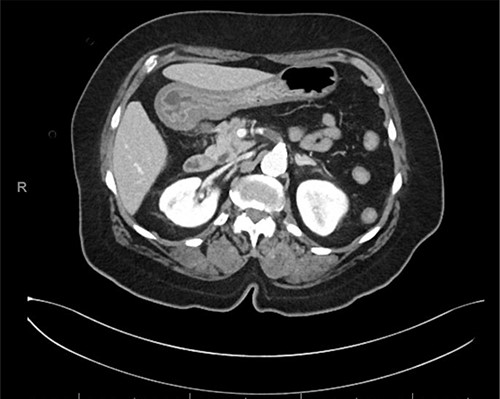

An 80-year-old female with a medical history of hypertension and type II diabetes mellitus presented to the emergency department with a 12-hour history of acute onset diffuse abdominal pain with nausea, vomiting and diarrhea. She had a past surgical history of cholecystectomy, no family history of arrhythmias or hypercoagulability and no history of smoking or illicit drug use. Initial vital signs were significant for blood pressure 217/123, heart rate 101 and oxygen saturation 91% on 5 L nasal cannula and a temperature of 36.6°C. On physical exam, she was noted to be in significant distress and writhing in pain. She was alert and oriented to person, time and place. She was noted to be in sinus tachycardia and tachypneic with diffuse crackles bilaterally. On abdominal exam, she was soft, non-distended and non-tender to palpation. Laboratory studies were significant for a lactic acid 2.4 on venous blood gas, a normal white blood cell count with 82% neutrophils and INR 1.23. Additionally, she was found to be positive for COVID-19 (cobas SARS-CoV-2 RT-PCR) and her stool assay was positive for C. difficile (Xpert C. difficile assay). Chest x-ray showed bilateral mild to moderate interstitial and ground glass opacities. CT abdomen and pelvis with intravenous (IV) contrast showed a 1.7 cm occlusion of the proximal SMA with distal reconstitution and no evidence of bowel ischemia (Fig. 1).

CT abdomen and pelvis with IV contrast, axial image of 1.7 cm occlusive thrombus of proximal SMA.